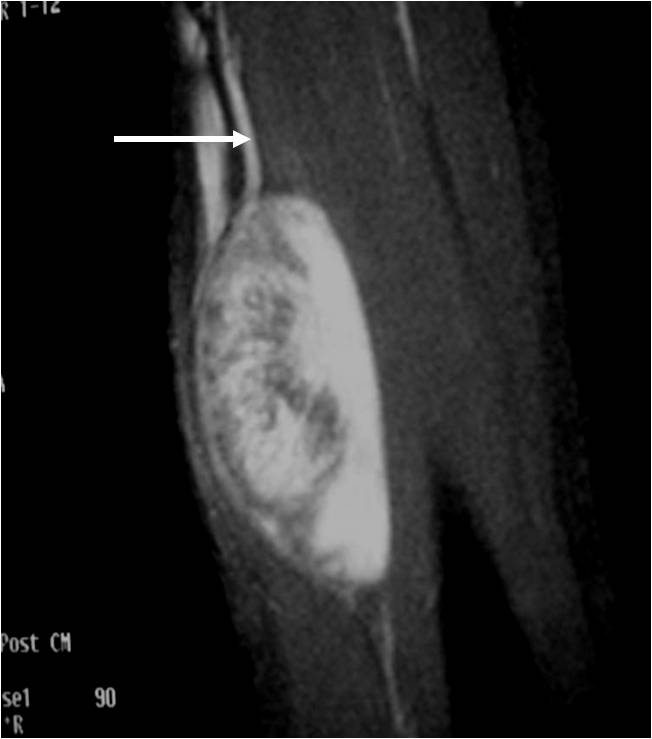

Radiographic imaging is used to help form a diagnosis. These include MRI, CT and Bone Scans.

An example of an MRI is shown.